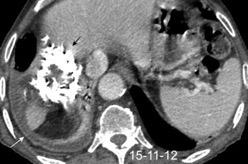

54. QUISTE HIDATÍDICO DIAFRAGMÁTICO

Quiste hidatídico pulmonar (¿implante cisural?) y hepático ¿perforado al espacio pleural?

M et al. Thoracic hydatid disease: A radiologic review of unusual cases. World J Clin Cases 2020

Quiste hidatídico hepático calcificado y pulmonar. Atelectasia LID asociada